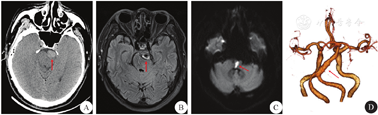

患者 男性,56岁,退休工人,因"头晕3 d,左侧肢体麻木无力17 h"于2019年10月就诊于浙江省人民医院神经内科。患者3 d前出现持续头晕伴行走不稳,伴恶心,17 h前出现左侧肢体无力伴麻木,口齿不清,由家人送至医院急诊。既往史:3年前因言语含糊至当地医院就诊,诊断为"脑梗死",未遗留明显后遗症,出院后自行停用阿司匹林及他汀类药物。个人史:否认吸烟及饮酒史,睡眠规律,大小便无异常。婚育及家族史无特殊。入院体检:神志清楚,对答切题,轻度构音障碍,咽反射下降,颈软无抵抗,克氏征阴性,双瞳等圆等大,直径3 mm,光反射存在,双眼水平眼震,两眼向右侧活动部分受限,双耳听力基本对称,左侧鼻唇沟偏浅,伸舌基本居中,额纹对称。右侧肢体肌力5级,左侧肢体肌力3级,肌张力正常,双侧腱反射(++),左侧巴氏征(+),右侧巴氏征(-),左侧面部和肢体针刺觉减退,四肢振动觉对称。洼田饮水试验:吞咽功能3级。入院后头颅CT提示椎基底动脉延长并扩张,脑干受压改变(图1A);头颅MRI提示基底动脉增宽,液体衰减反转恢复(fluid attenuated inversion recovery,FLAIR)序列可见血管高信号征(图1B),DWI提示桥脑延髓急性脑梗死(图1C);头颅CT血管成像(CT angiography,CTA)提示基底动脉增粗,直径约9 mm,走行迂曲(图1D);经颅多普勒超声(transcranial doppler,TCD)提示基底动脉收缩期血流峰值流速32 cm/s,低于正常值(40~70 cm/s)。

A:CT提示椎基底动脉扩张,脑干受压(箭头所示);B:MRI T2加权FLAIR序列血管高信号征(箭头所示);C:DWI示桥脑延髓斑片状高信号(箭头所示);D:CTA示双侧椎动脉V4段、基底动脉增粗,径约9 mm,走行迂曲(箭头所示);FLAIR:液体衰减反转恢复;CTA:CT血管成像